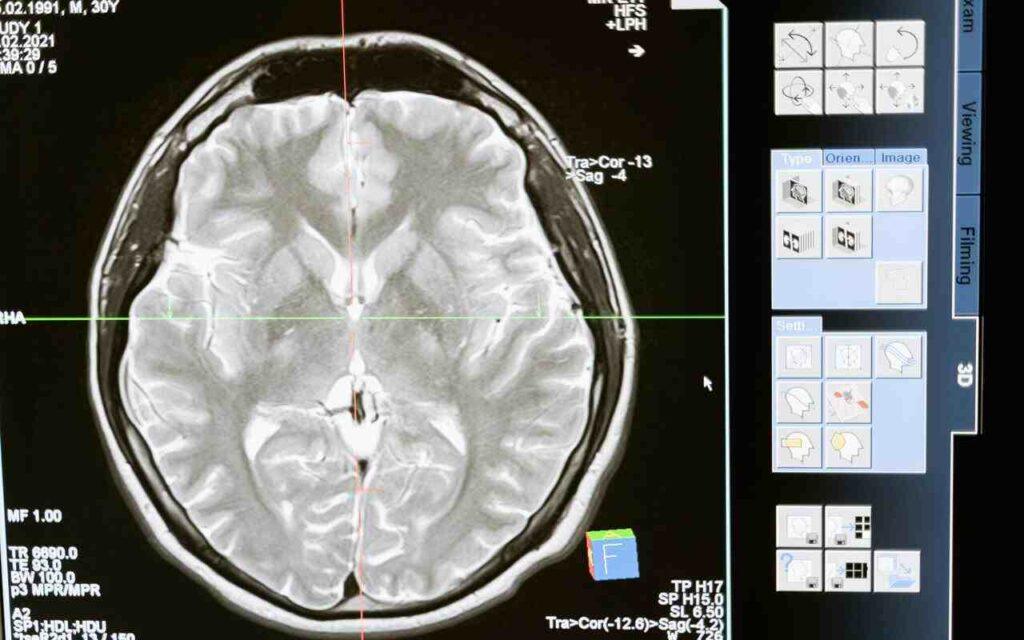

L’encefalo è formato da cervello, diencefalo, tronco encefalico, cervelletto. Prima di entrare nel vivo delle sue funzioni, parliamo di encefalo significato. Il termine deriva dalla parola greca ἐγκέϕαλος, che si può tradurre con il termine italiano “dentro la testa”.

Come sopra ricordato, nell’ambito delle parti dell’encefalo è possibile includere anche il cervello, conosciuto anche come telencefalo. Rispetto alle altre, è la parte più voluminosa e con un maggior grado di specializzazione.

Entrando nel vivo di tutto quello che ruota attorno ad aree del cervello e funzioni, è doveroso citare gli emisferi cerebrali. Cosa sono? Due masse semisferiche di tessuto nervoso, praticamente simmetriche.

Caratterizzato da uno strato superficiale laminare, ossia la corteccia cerebrale, presentano, internamente, ammassi di sostanza bianca e nuclei di piccole dimensioni di sostanza grigia.

Cosa altro dire sull’anatomia encefalo? Oltre agli aspetti sopra citati, è il caso di chiamare in causa la protezione da parte della barriera emato-encefalica. Grazie alla presenza di quest’ultima, è impedito l’arrivo a quest’organo vitale di alcune sostanze tossiche che circolano nel sangue.